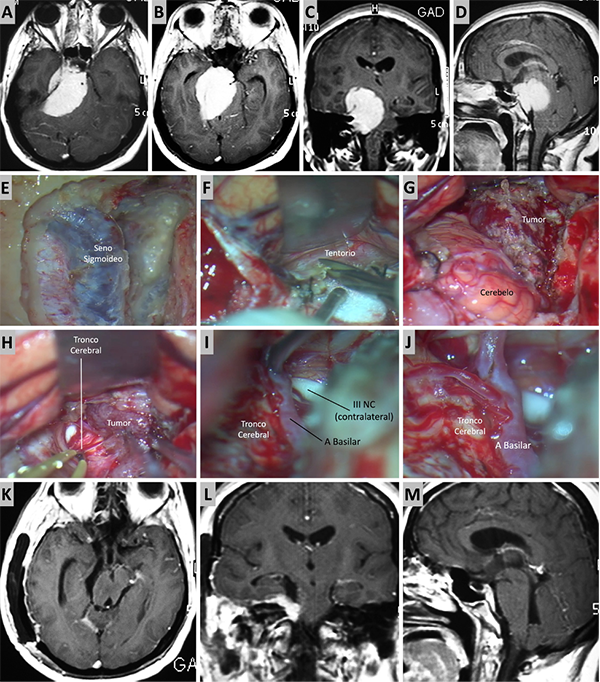

Figura 8. Caso ilustrativo #6. Resonancia que muestra MRPC con implantación petroclival y extensión a la fosa media. A-D. Se presentan las imágenes prequirúrgicas, corte axial, coronal y sagital. E-J. Se realizo un abordaje presigmoideo combinado con un abordaje subtemporal, logrando una exposición del seno sigmoideo y una visión directa del tumor consiguiendo una resección total. K-M. RMN posquirúrgica donde se observa una resección quirúrgica total.